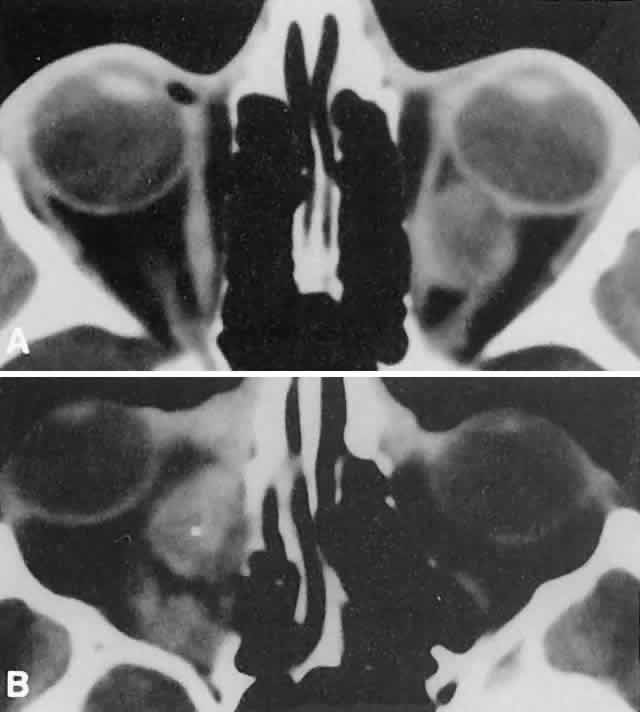

Within the orbit, rhabdomyosarcoma occurs most often, but not exclusively, in the superior nasal quadrant, with downward and outward displacement of the globe. CT scans show the topography of the orbital mass (Fig. 1A), as well as the possible extension into adjacent bone, paranasal sinuses, or the intracranial cavity. The circumscription that may be noted on CT is relative, because the lesion is not encapsulated and microscopically infiltrates normal tissue. Echography shows internal echoes of low-to-medium amplitude. Because the cellular tumor absorbs acoustic energy, the amplitude of the spikes falls off somewhat through the lesion (see Fig. 1B and C). MRI can help define the tumor's relationship to extraocular muscles (Fig. 2).

Fig. 1. A. Proptosis and downward, outward globe displacement developed over 2 days in a 3-year-old girl. A homogeneous mass fills the superomedial orbit. B. Contact B-scanning shows a relatively well-circumscribed mass with uniform internal echoes. C. Contact A-scanning shows the internal reflectivity to be of low to medium amplitude, consistent with a sarcomatous lesion. Biopsy results confirmed the diagnosis of rhabdomyosarcoma.

Orbital myositis may represent a greater proportion of cases of IIPT in childhood than in adulthood, and involvement of multiple extraocular muscles may occur more frequently in children than inadults. In orbital myositis, early diplopia and increased discomfort with attempted eye movement are typical symptoms. CT may show enlargement of one or more extraocular muscles in one or both orbits (Figs. 21 and 22). When a single muscle is involved, the specter of a primary or metastatic neoplasm within the muscle may be raised. However, external inflammatory signs, considerable pain and limited motility, and an explosive onset of symptoms within 24 hours all suggest orbital myositis. The uniform enlargement of the muscle, including its tendinous insertion (see Fig. 22), also helps distinguish the process from a neoplasm, which might be expected to produce a more focal, globular expansion. Echography may support the diagnosis of inflammation by showing edema in the episcleral space as a relative sonolucency between the scleral and orbital fat echoes (Fig. 23). Its CT counterpart is an increase in the radiodensity and thickness of the ocular tunica.

Fig. 21. A. This 16-year-old boy had acute onset of bilateral proptosis, pain, diplopia, chemosis, and conjunctival injection. B. Bilateral enlargement of the superior and medial rectus and inferior oblique muscles. Other sections showed similar involvement of other extraocular muscles.

Fig. 22. The uniform enlargement of the left medial rectus muscle, including its tendinous insertion, is characteristic of orbital myositis.

Fig. 23. Acoustic discontinuity between the globe and the orbital fat indicates inflammatory edema in Tenon's space.

Fig. 24. A. Nonbacterial dacryoadenitis may be unilateral or bilateral. External inflammatory signs are maximal in the superotemporal quadrant. B. The left lacrimal gland is enlarged, with a shape molded by the globe and orbital walls. A neoplasm usually can be ruled out by analysis of the history, CT findings, and echographic characteristics, but a biopsy may be required in equivocal cases.